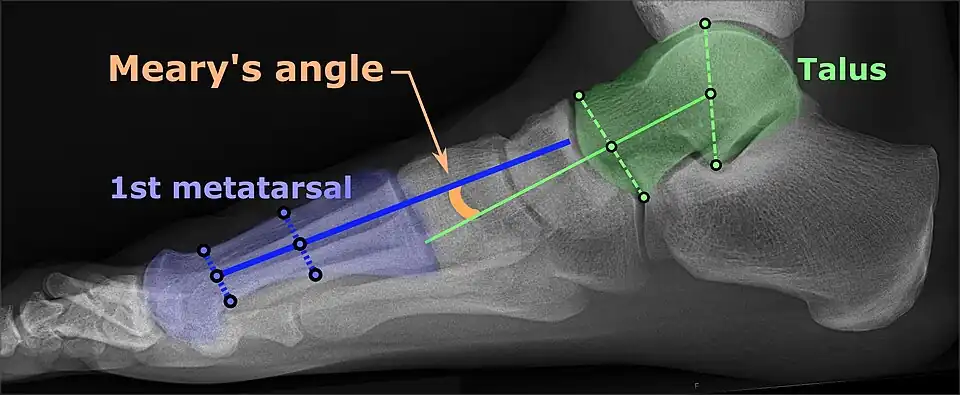

On weightbearing projectional radiography, pes cavus can be diagnosed and graded by several features, the most important being medial peritalar subluxation, increased calcaneal pitch (variable) and abnormal talar-1st metatarsal angle (Meary's angle).[14] Medial peritalar subluxation can be demonstrated by a medially rotated talonavicular coverage angle.[14]

Same lateral X-ray showing the measurement of Meary's angle, which is the angle between the long axis of the talus and first metatarsal bone.[14] This example is slightly convex downward. An angle greater than 4° convex upward is considered pes cavus.[14] -